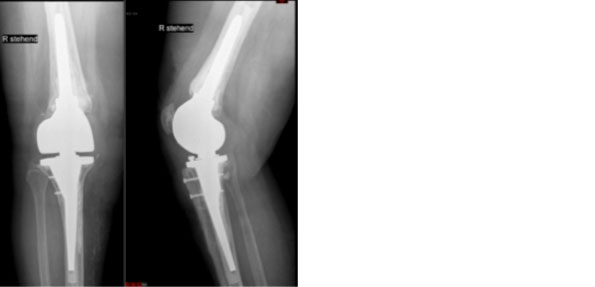

Beipiel einer gelockerten Knieprothese